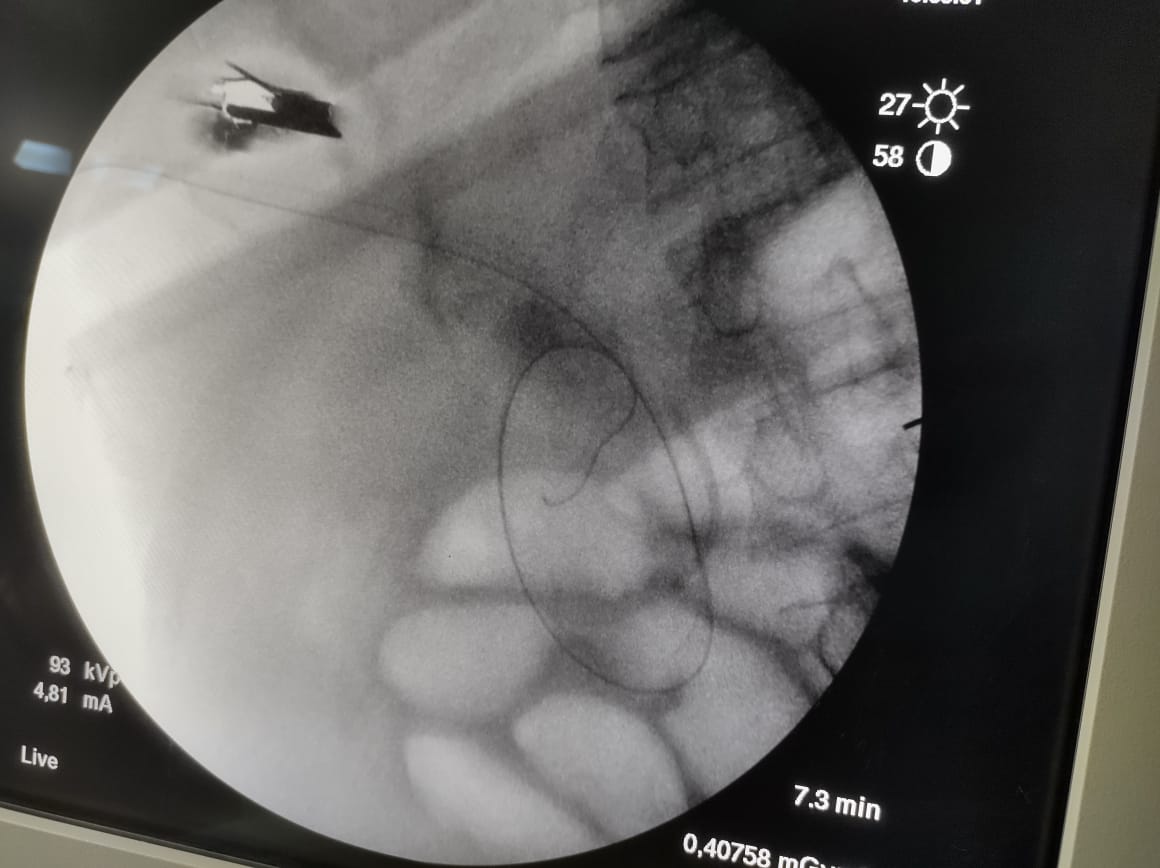

وقال بيان الهيئة، أنه تم إجراء عملية (راندڤو) ناجحة لمسن يعاني من صفراء انسدادية، وخلال العملية يتم استخدام المنظار والأشعة التداخلية معًا، وذلك لأول مرة تحت مظلة التأمين الصحي الشامل الجديدة، مشيرًا إلى أنه بمراجعة التاريخ المرضي للمنتفع، تبين أنه قام بإجراء عملية قلب مفتوح منذ ٧ أشهر، مع وجود فشل في وظائف القلب وارتجاع في الصمام المترالي.

وتابع البيان، تم عمل محاولتين لعمل منظار قنوات مرارية للمنتفع المشار إليه، وكانتا غير ناجحتين، وعليه تم تحضير المريض لإجراء عملية (راندڤو)، والتي تتم بمشاركة استشاري المناظير مع استشاري الأشعة التداخلية، وذلك لإزالة سبب انسداد القنوات الصفراوية مع تركيب دعامة له، وذلك تحت مظلة التأمين الصحي الشامل، دون تحميل المريض أكثر من 300 جنيه فقط نسبة مساهمة.

واستكمل الدكتور مصطفى شعبان، مدير فرع الهيئة ببورسعيد، أن مزايا عمليات المناظير عديدة لا تتوافر في الجراحات المفتوحة مثل سرعة التعافي وقِصر المكوث في المستشفى والعودة السريعة لممارسة الحياة الطبيعية، لافتًا أن تقنية (راندڤو) هي تقنية تجرى لأول مرة على أرض بورسعيد، وأطلق عليها هذا الاسم حيث يتلاقى المنظار والأشعة التداخلية داخل جسم المريض، بالمنطقة المصابة خلال العملية، مؤكدًا نجاح العملية وتماثل المريض للشفاء.